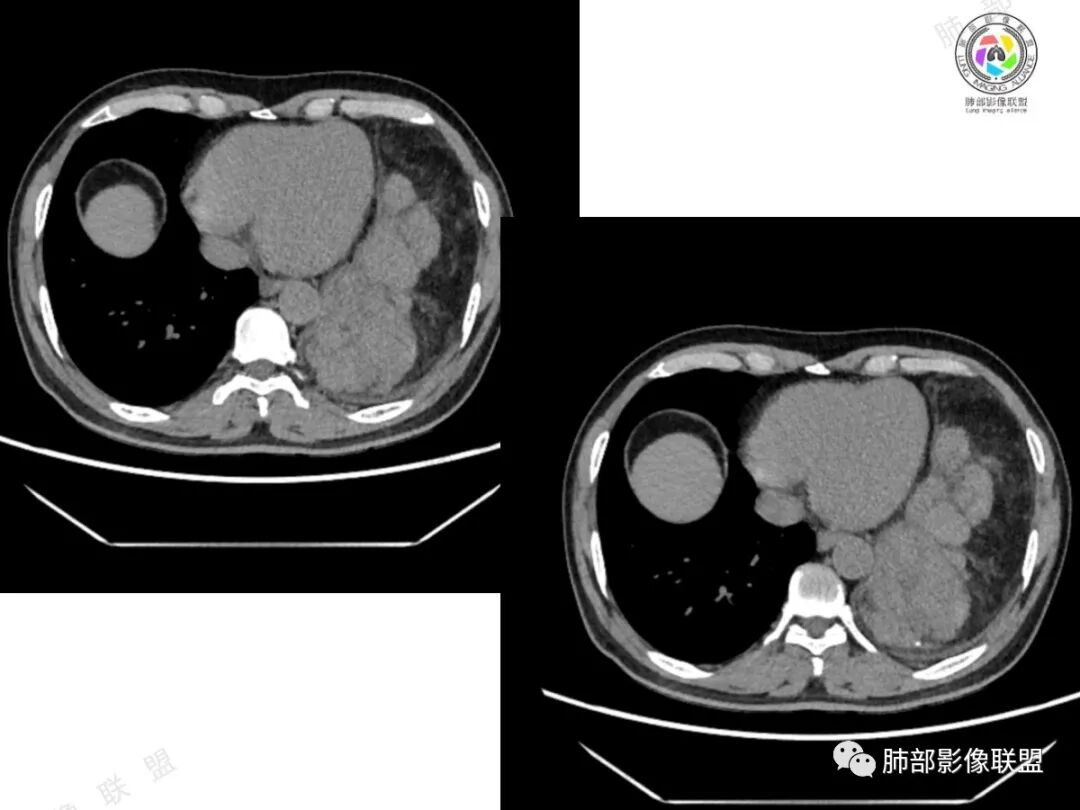

结果:碰撞瘤

胸腺瘤伴畸胎瘤

2、影像所见:左侧纵隔紧贴心包铸型生长巨大混杂密度肿块,边界清楚,临近结构受推挤移位,无明显外侵征象。肿块自主动脉弓旁一直顺延到至膈顶,呈“垂乳征”。病灶脂肪成分居多,斑片状、结节状及团块状实性密度成分散落其中,呈地图样分布,实性成分偶见低密度线样分隔,未见明确钙化影。增强扫描实性成分呈延迟明显强化,并见强化血管影。纵隔内有肿大淋巴结,未见胸腔积液,肺内及胸膜未见转移性病灶。

④胸腺瘤:常见于40岁以上患者,是最常见的前纵隔肿瘤,大多数位于前纵隔,其次为心包旁,常偏侧生长,多数密度均匀,大于15㎝罕见,一般轻-中度强化,少数可明显强化。黄勇老师认为,胸腺瘤病理标本上均伴有不同程度间隔存在,随着侵袭性增强,分隔会逐渐不显著。当病灶有明确分隔,较均匀强化时,胸腺瘤一定要考虑到。

4、疑惑:本例临床病史与影像表现,似乎单纯用一元论不足以解释全部,故要考虑到有无二元共存的可能性。

碰撞瘤是发生在同一解剖部位上的2种不同组织来源的肿瘤,肿瘤成分之间通过薄层基质或各自的基板分隔,2种肿瘤邻近但肿瘤组织无混合。

碰撞瘤的概念包括以下含义:(1)在同一解剖部位发生;(2)内部含有2种能明确区分的肿瘤;(3) 2种肿瘤组织相邻,但没有肿瘤细胞或组织的混合。